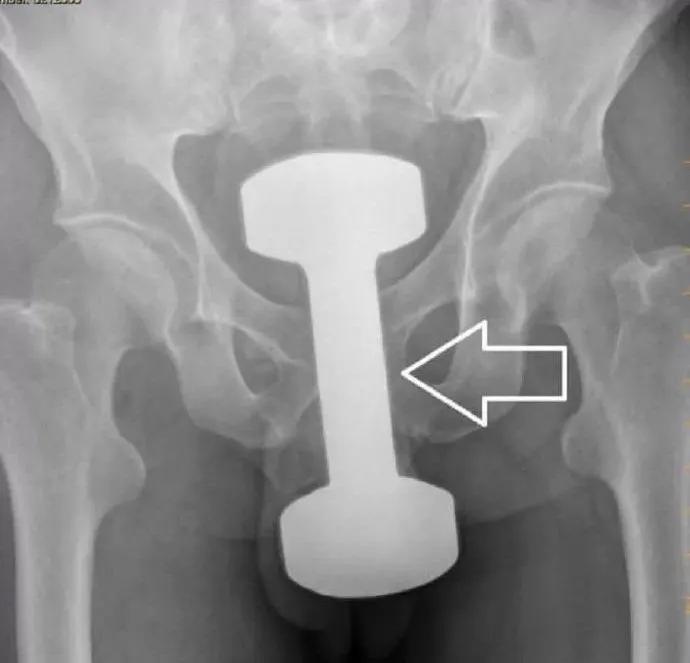

直肠不直,容易卡住!

直肠虽然叫做直肠,但它绝不是直的,有2个弯曲和3个侧曲。有个膨大的地方叫做壶腹,特别容易存东西。

肛柱、肛窦、肛瓣,使得直肠很不平坦。

以上结构使得经口吞入的长条型物体容易嵌顿于转弯处,针刺样物体容易阻留于直肠窦处,而经肛门进入的物体容易吸到直肠壶腹部。

还有“把门”的括约肌

正常的肛门括约肌一般处于闭合状态,借用外力往肛门里塞入异物时比较容易,异物塞入后括约肌回缩,像给肛门口“上锁”一样,取出时就变得困难。异物可能会引起肠梗阻、肠道水肿、感染,甚至损伤肠管导致肠穿孔,危及生命!